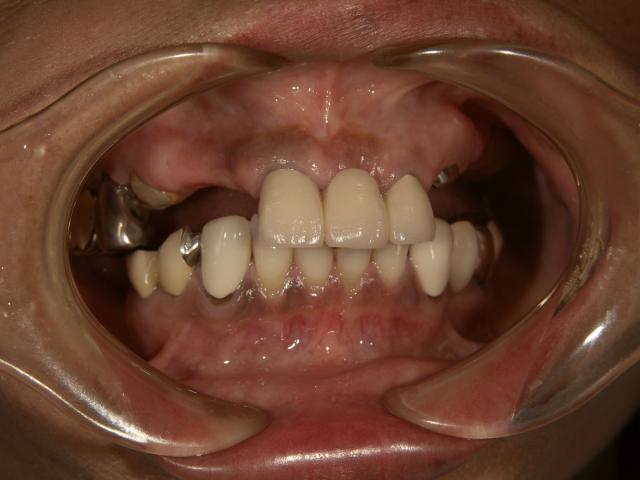

金属の針金なしの入れ歯 ノンクラスプデンチャー

2006/04/20

70代女性

院長担当

かみ合わせが交差した咬合

金属の針金なしの入れ歯

下唇のツッパリが消えて自然なアーチを描いてます。

唇のふくらみの回復、自然観見て下さい!

唇を上に上げても金属は見えず、歯肉も自然です!